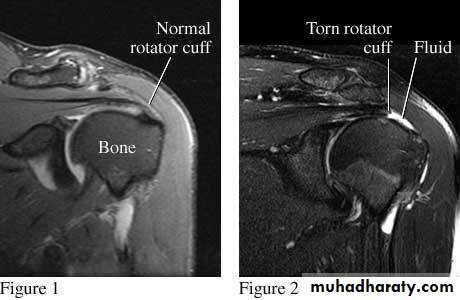

2.MRI

.Rotator cuff tears of the shoulder .